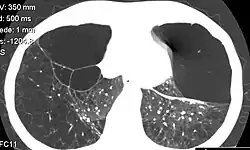

Una bulla pulmonar (del latín bulla, burbuja) consiste en una bolsa de aire (neumatosis) con paredes fina (hasta 1 mm) s que contiene aire dentro de un pulmón, resultado de la destrucción, dilatación y confluencia de espacios aéreos distales a los bronquiolos terminales. Puede ocasionar falta de aire (disnea), neumotórax espontáneo y abscesos.

Hay que distinguir las bullas pulmonares de otras lesiones con apariencia semejante en la radiografía de tórax, como son las cavidades o cavitaciones pulmonares, estas tiene una pared más gruesa (mayor de 4 mm) y los quistes pulmonares con paredes de ente 1 y 4 mm.[1]

Las bullas en el paciente con enfisema pulmonar se caracteriza por la existencia de amplias áreas de pulmón hiperclaro surcadas por tractos lineales curvilíneos que no corresponden a ninguna estructura anatómica reconocible y que correspondan a las propias paredes de las bullas[2]